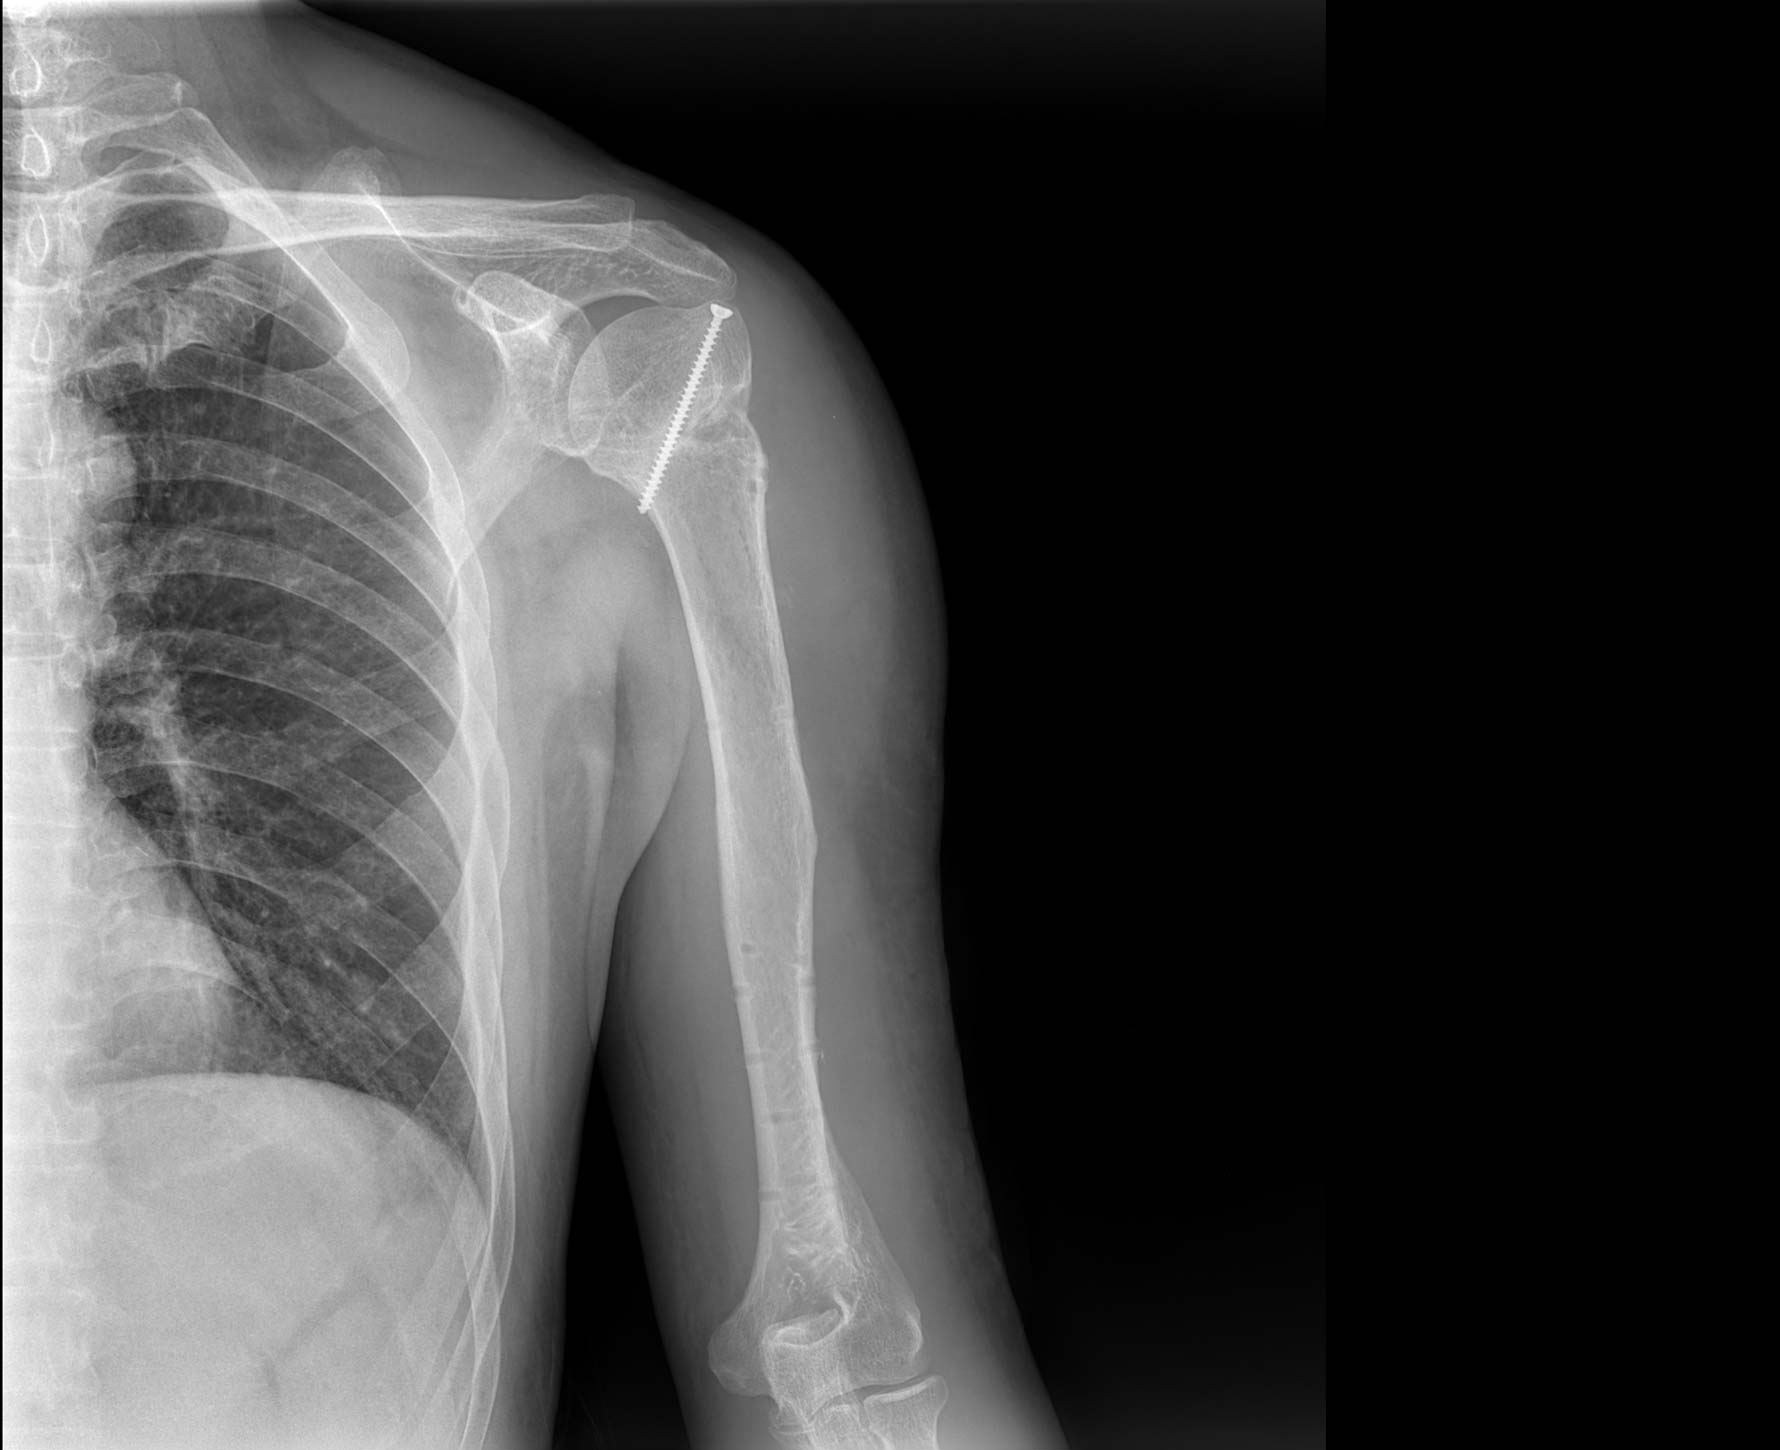

• 拍片

适用于全身各部位摄影

(常规摄影和特殊摄影)